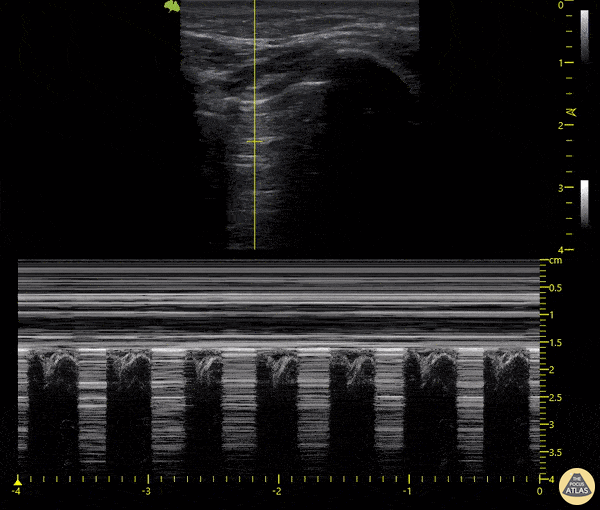

What is the sign shown in this lung scan:

Lung Point